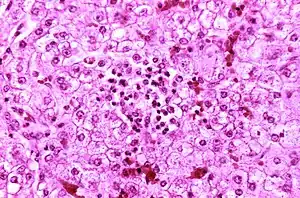

| Appearance of a liver from a child who died of Reye syndrome as seen with a microscope. Hepatocytes are pale-staining due to intracellular fat droplets. | |